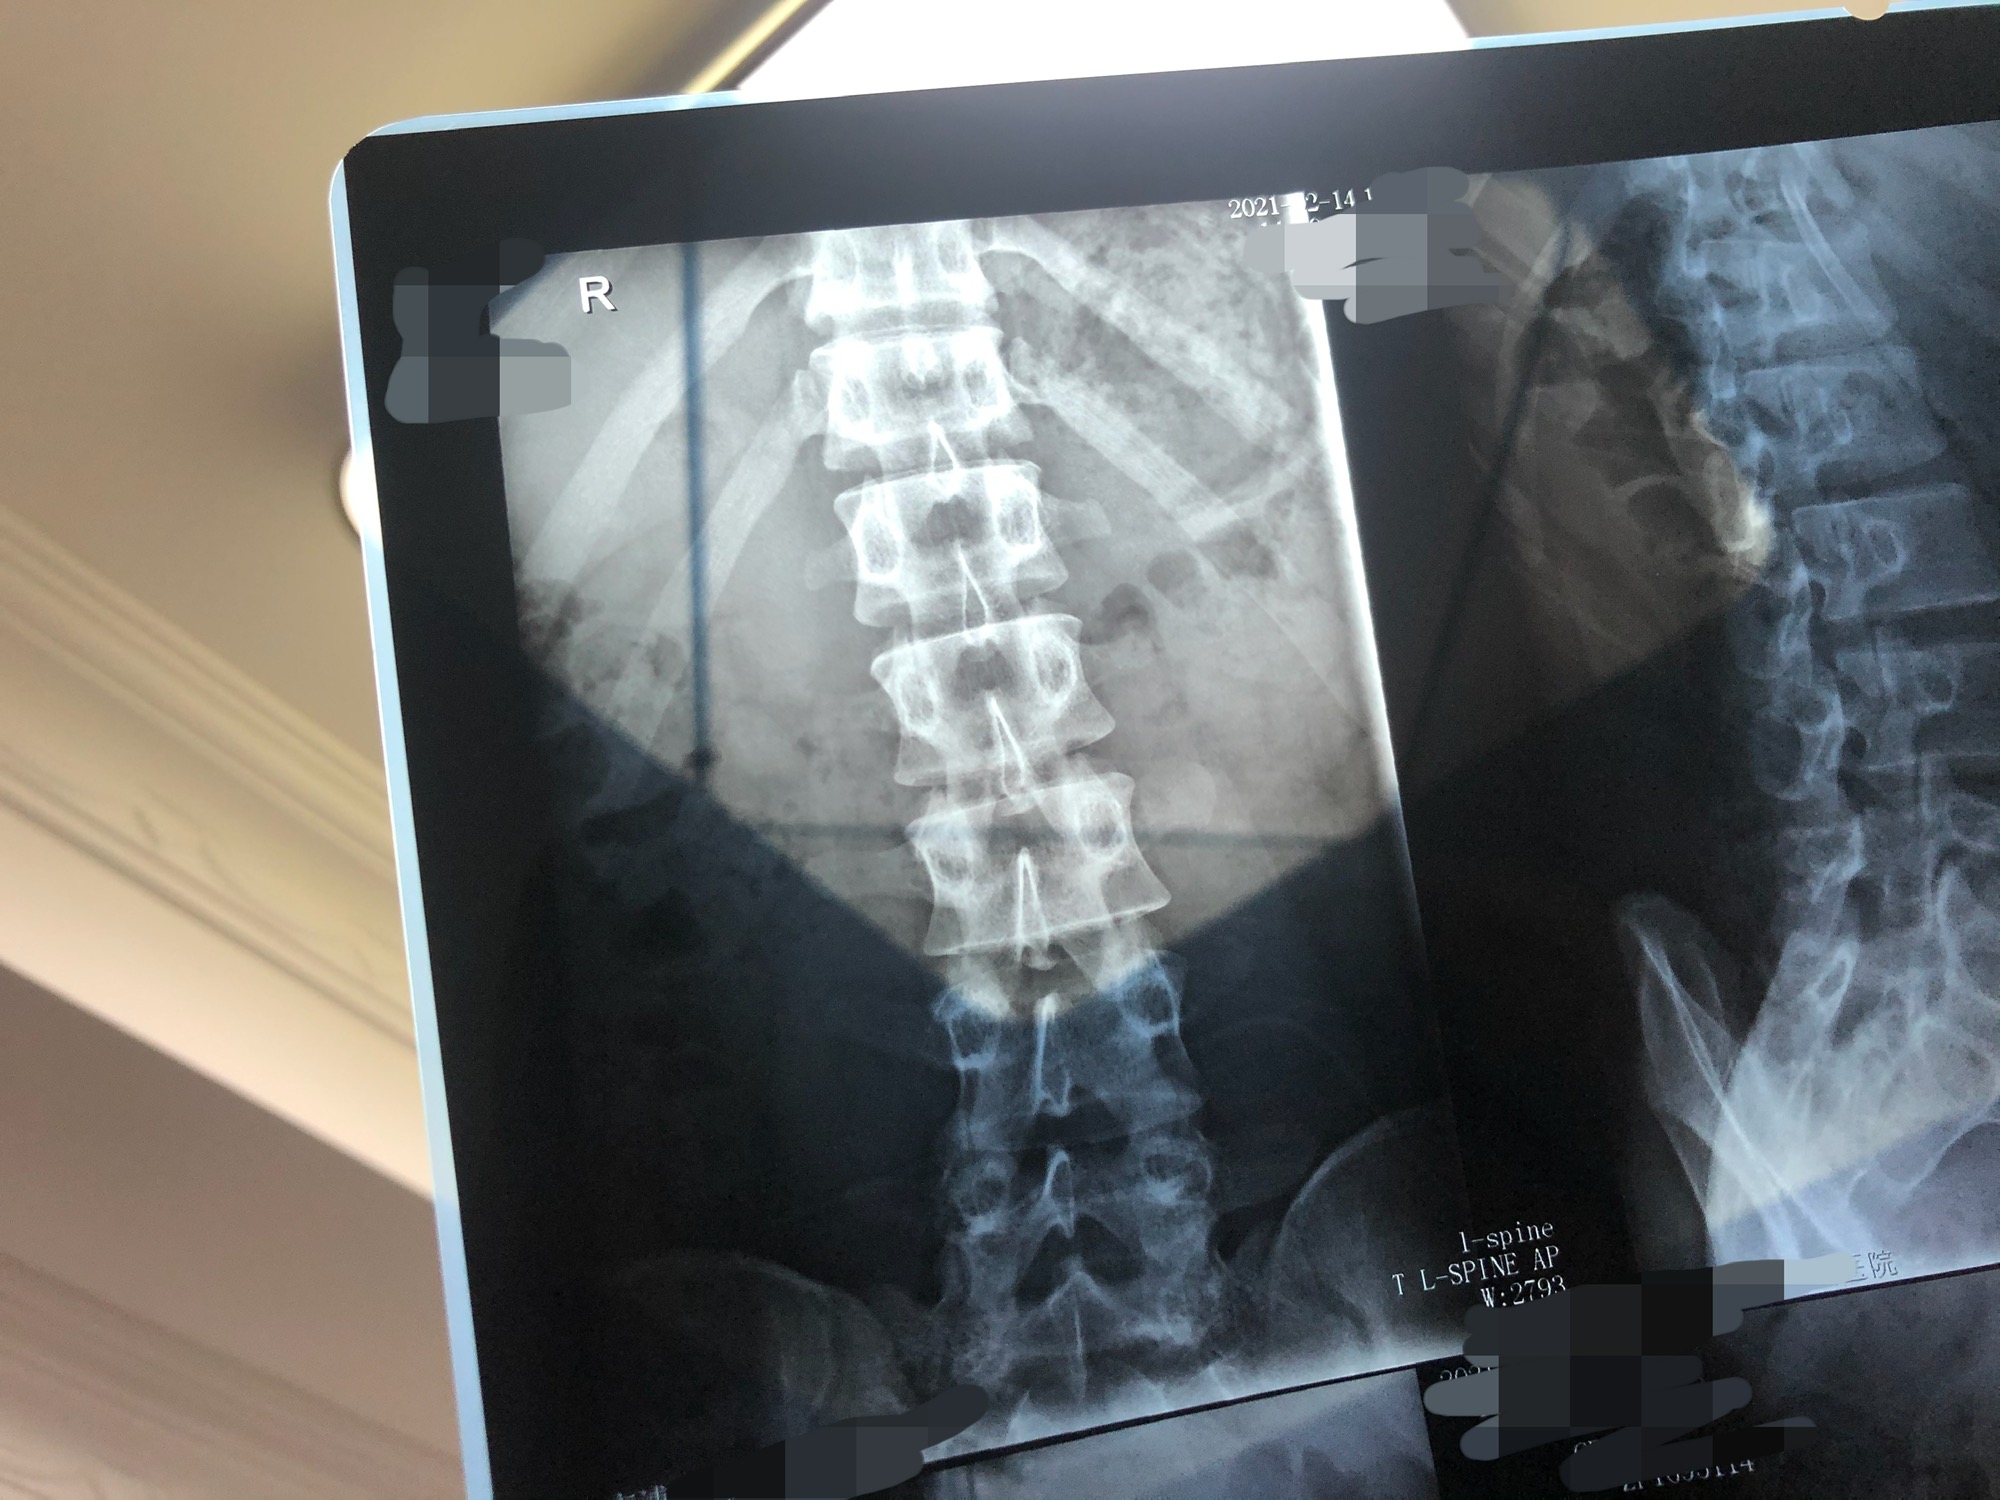

即刻的家人们一定一定一定要注意坐姿!!

前几天因为久坐在电脑前,左手搭在下巴上,右手握鼠标,图轻松。从除夕开始坐骨就有不适感了!医生诊断是筋膜炎和软组织挫伤。有时候会注意到脊骨偏了,但渐渐又斜过来,结果就是CT上的脊柱偏移。(正常范围内)

朋友们一定要注意坐姿!不要久坐!不要像我这样!